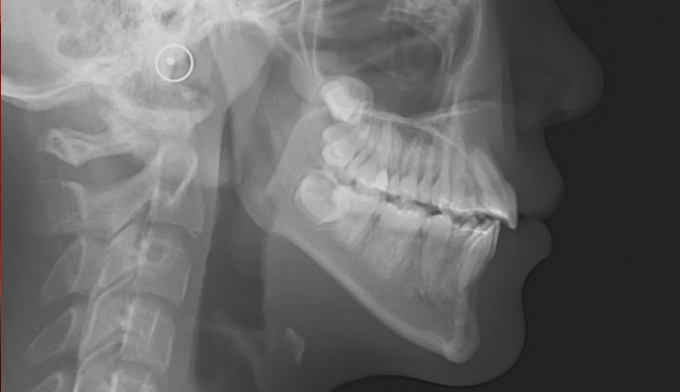

좁은 위턱을 확장하여 치아를 배열할 공간을 만들어주었고, 이 공간을 이용해 치아를 배열합니다.

아래턱의 과성장이 심해지고 있어서 절충치료로 아래치열을 배열해줍니다.

이미 송곳니와 작은어금니의 위치가 꽤 많이 바뀐 상태에서 치과에 내원하게 되어 어쩔 수 없이 최종적인 위치를 바꿔서 배열합니다. 씹거나 말하는데는 전혀 문제가 없습니다.

총 치료기간은 26개월 입니다.

아이의 성장기에는 주기적으로 치과에 내원하여 치아의 맹출 방향이 올바른지, 방해되는 요소는 없는지 확인하여야 합니다.